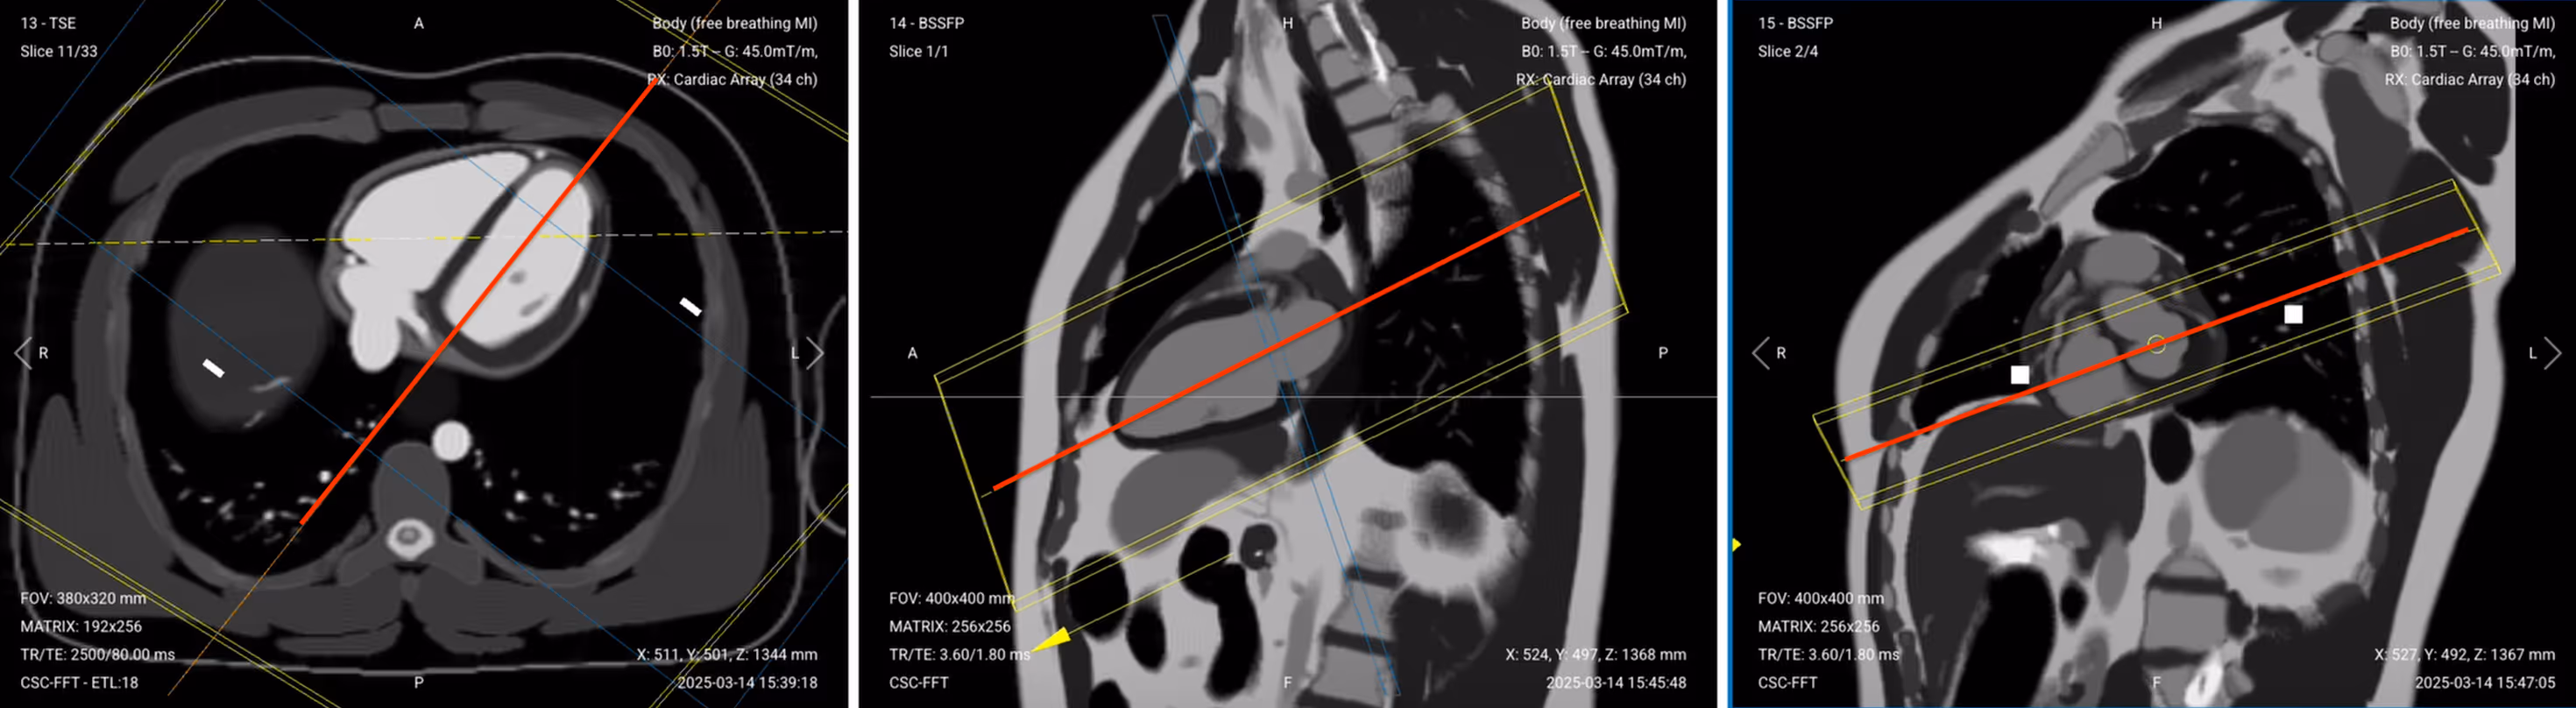

This localizer helps us plan the actual diagnostic sequences by capturing a preliminary view of the left atrium and left ventricle.

✅ Correct Planning:

Planning Instructions:

This localizer creates a perpendicular reference to the two-chamber view for planning the cine sequences. This stack helps identify structures to exclude later when refining the final 2-chamber view.